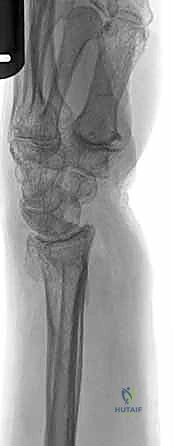

1. الأشعة السينية (X-rays): بوضعيات متعددة (أمامية خلفية، وجانبية دقيقة). الوضعية الجانبية الحقيقية (True Lateral) حاسمة لاكتشاف أي خلع جزئي في المفصل (DRUJ).

2. الأشعة المقطعية ثلاثية الأبعاد (3D CT Scan): تُستخدم في الكسور المفتتة أو كسور رأس الزند المفصلية المعقدة، حيث تعطي خريطة دقيقة للجراح قبل الدخول لغرفة العمليات.

3. الرنين المغناطيسي (MRI): يُطلب عند الاشتباه القوي بوجود تمزقات في الأربطة والمركب الغضروفي (TFCC) التي لا تظهر في الأشعة السينية.

الأعراض والتشخيص السريري الدقيق مع الأستاذ الدكتور محمد هطيف

عند تعرض المريض لإصابة في الساعد أو المعصم، فإن سرعة التشخيص ودقته هما مفتاح العلاج الناجح. يتميز الأستاذ الدكتور محمد هطيف باتباع بروتوكول تشخيصي صارم يضمن عدم إغفال أي تفصيل صغير قد يؤثر على مستقبل وظيفة يد المريض.